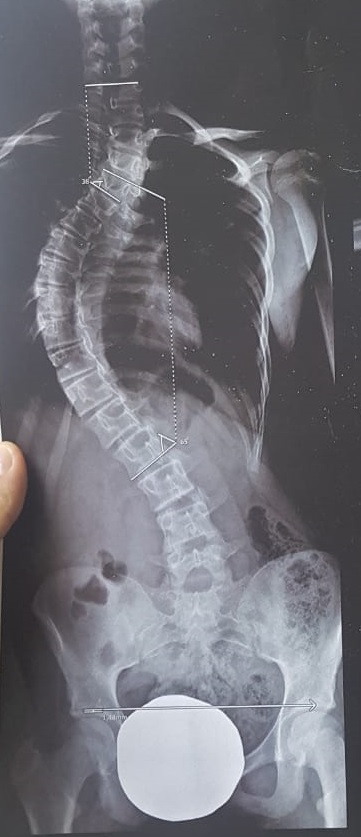

Cirugía de deformidad: Tratamiento de escoliosis idiopáticas o congénitas, para evitar el empeoramiento de la curva de la columna y devolver la estabilidad y estética de los pacientes. Dichas cirugías se realizan por técnica convencional debido a que necesitan correcciones amplias.